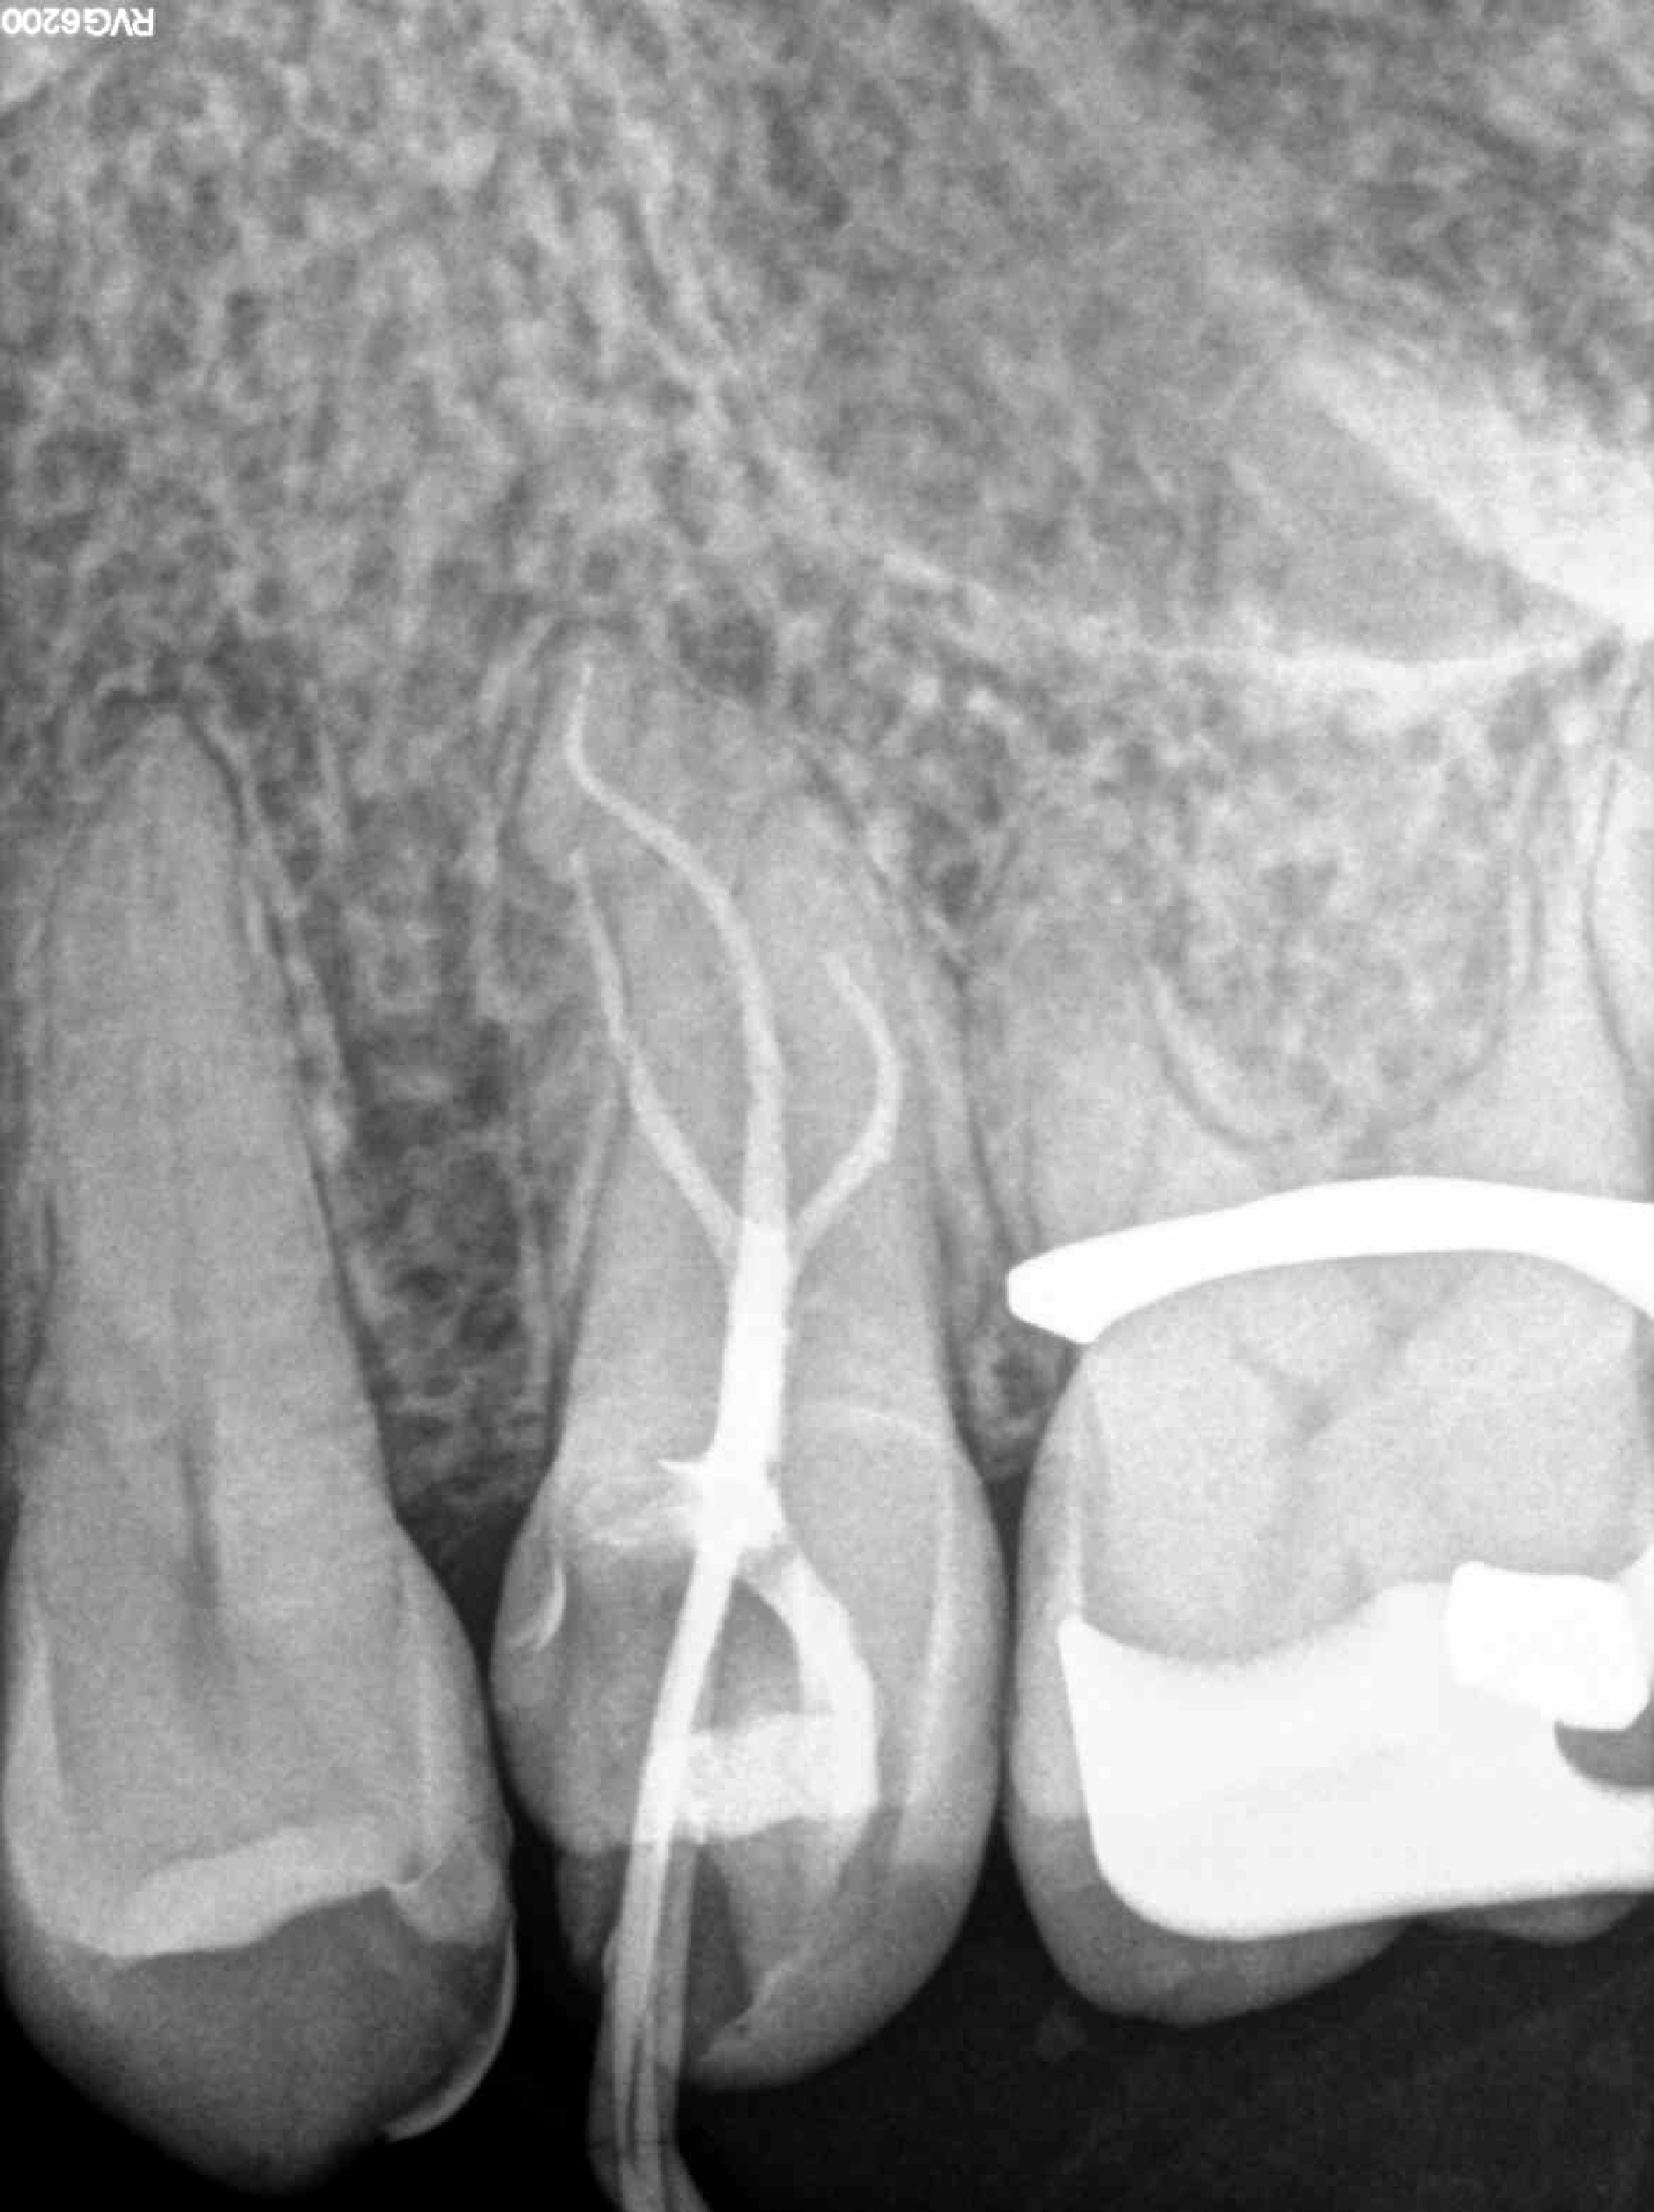

* Haz click sobre las radiografías para verlas a mayor tamaño

Haz click sobre las radiografías para verlas a mayor tamaño